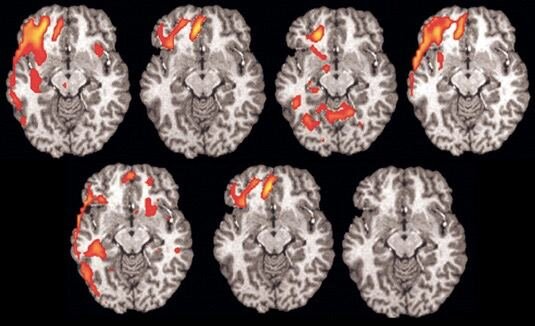

Нейробиологи из Швейцарии просканировали мозг 13 взрослых людей и обнаружили, что звуки положительно окрашенного голоса вызывают сильную нейронную активность и положительные эмоции, когда они слышны именно с левой стороны.Сейчас ученые выясняют для чего нашему мозгу такое разделение.